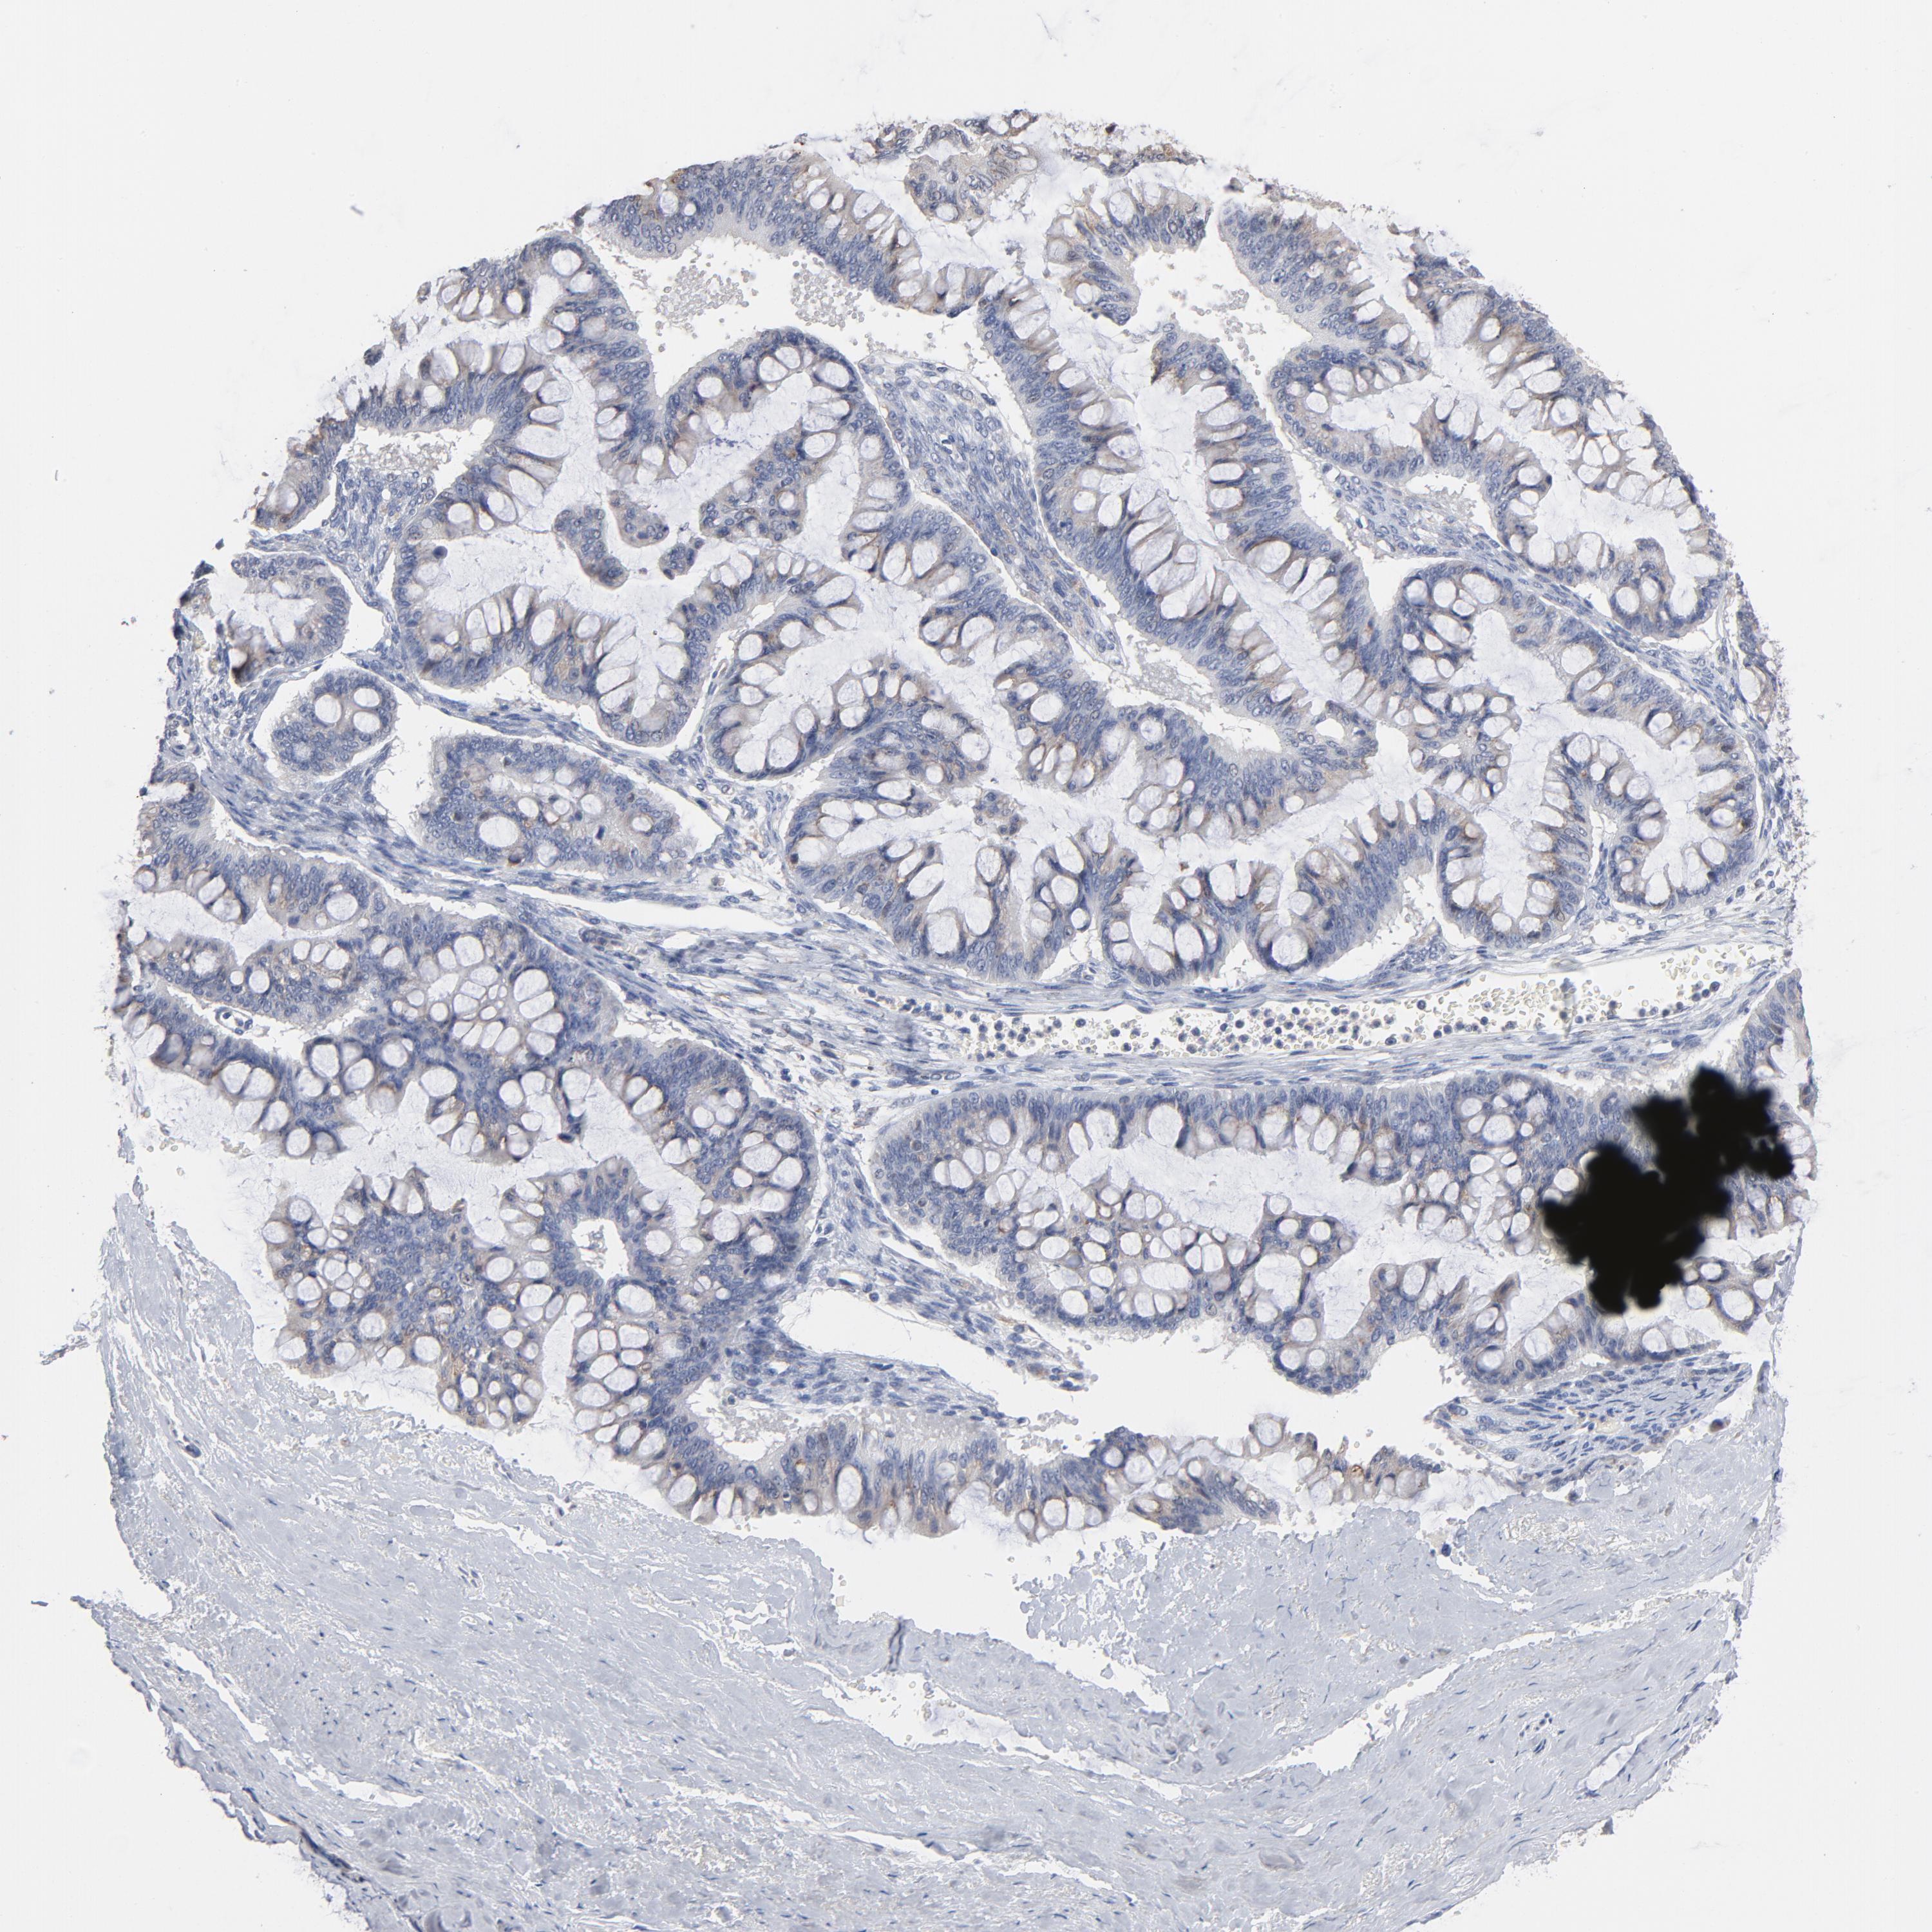

OVARIAN CANCER - Protein expressioni

A mouse-over function shows sample information and annotation data. Click on an image to view it in a full screen mode. Samples can be filtered based on level of antibody staining by selecting one or several of the following categories: high, medium, low and not detected. The assay and annotation is described here.

Note that samples used for immunohistochemistry by the Human Protein Atlas do not correspond to samples in the TCGA dataset.

Antibody stainingi

Antibody staining in the annotated cell types in the current human tissue is reported as not detected, low, medium, or high, based on conventional immunohistochemistry profiling in selected tissues. This score is based on the combination of the staining intensity and fraction of stained cells.

Each image is clickable and will lead to virtual microscopy that enables deeper exploration of all samples and also displays staining intensity scores, fraction scores and subcellular localization as well as patient and tissue information for each sample.

Antibody HPA003543

Staining

High

Medium

Low

Not detected

Intensity

Strong

Moderate

Weak

Negative

Quantity

>75%

75%-25%

<25%

None

Location

Nuclear

Cytoplasmic/membranous

Cytoplasmic/membranous,nuclear

Cystadenocarcinoma, serous, NOS

Cystadenocarcinoma, mucinous, NOS

Carcinoma, endometroid